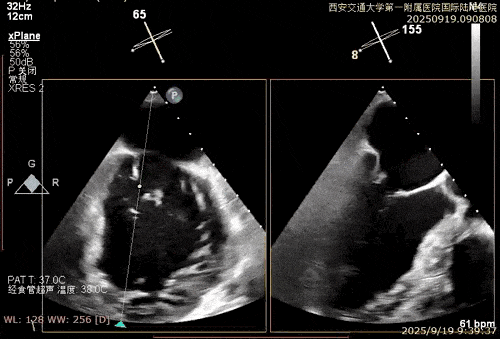

术中在超声引导下完成房间隔穿刺,将第一枚XTR在左房内完成终定位,2偏3区完成植入,夹合效果良好,即刻超声显示轻微反流,完成夹子释放,手术效果良好,手术圆满结束,患者术后6小时即实现床旁活动。